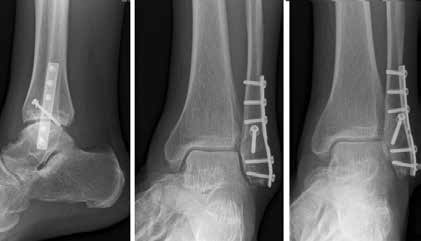

Arthrose stellt weltweit die häufigste Gelenkerkrankung dar und hat damit einen wesentlichen sozioökomischen Einfluss 1. Während 15 % der weltweiten erwachsenen Bevölkerung von Arthrose betroffen sind 2, leiden lediglich 1 % der Bevölkerung 3 bzw. 4,4 % der Arthrosepatienten 4 an einer Arthrose des oberen Sprunggelenks (OSG). Circa 80 % der Arthrosen des OSG sind ursächlich als posttraumatisch einzustufen, nur 9 % gelten als primäre Arthrosen. Dies unterscheidet die Arthrose des OSG von Coxarthrose (58 % primär) und Gonarthrose (67 % primär). 13 % treten im Rahmen systemischer Erkrankungen wie rheumatoider Arthritis, Hämochromatose, Hämophilie oder Osteonekrose auf 5 6. Die posttraumatische Arthrose des OSG wird besonders nach in Achsabweichung verheilten Frakturen (Pilon-tibiale-Frakturen, Weber-A‑, ‑B- und ‑C-Frakturen; Abb. 1a), Bandinstabilitäten des lateralen und medialen Bandapparates des OSG (Lig. fibulotalare anterius, Lig. fibulocalcaneare, Lig. fibulotibiale posterius etc.), nach rezidivierenden ligamentären Verletzungen sowie nach Gelenkverletzungen mit Knorpelschaden, „flake fractures“ oder „bone bruise“ beobachtet 7. Daher ist bei den vergleichsweise häufigen Weber-B- und ‑C-Frakturen die osteosynthetische Versorgung mittels Drittelrohrplatte und Zugschraube (Abb. 1b) sowie ggf. Syndesmosennaht mit Implantation einer Stellschraube mit millimetergenauer Reposition essentiell, um langfristig die Funktionsfähigkeit des OSG aufrechtzuerhalten und eine frühzeitige posttraumatische Arthrose zu verhindern 8.